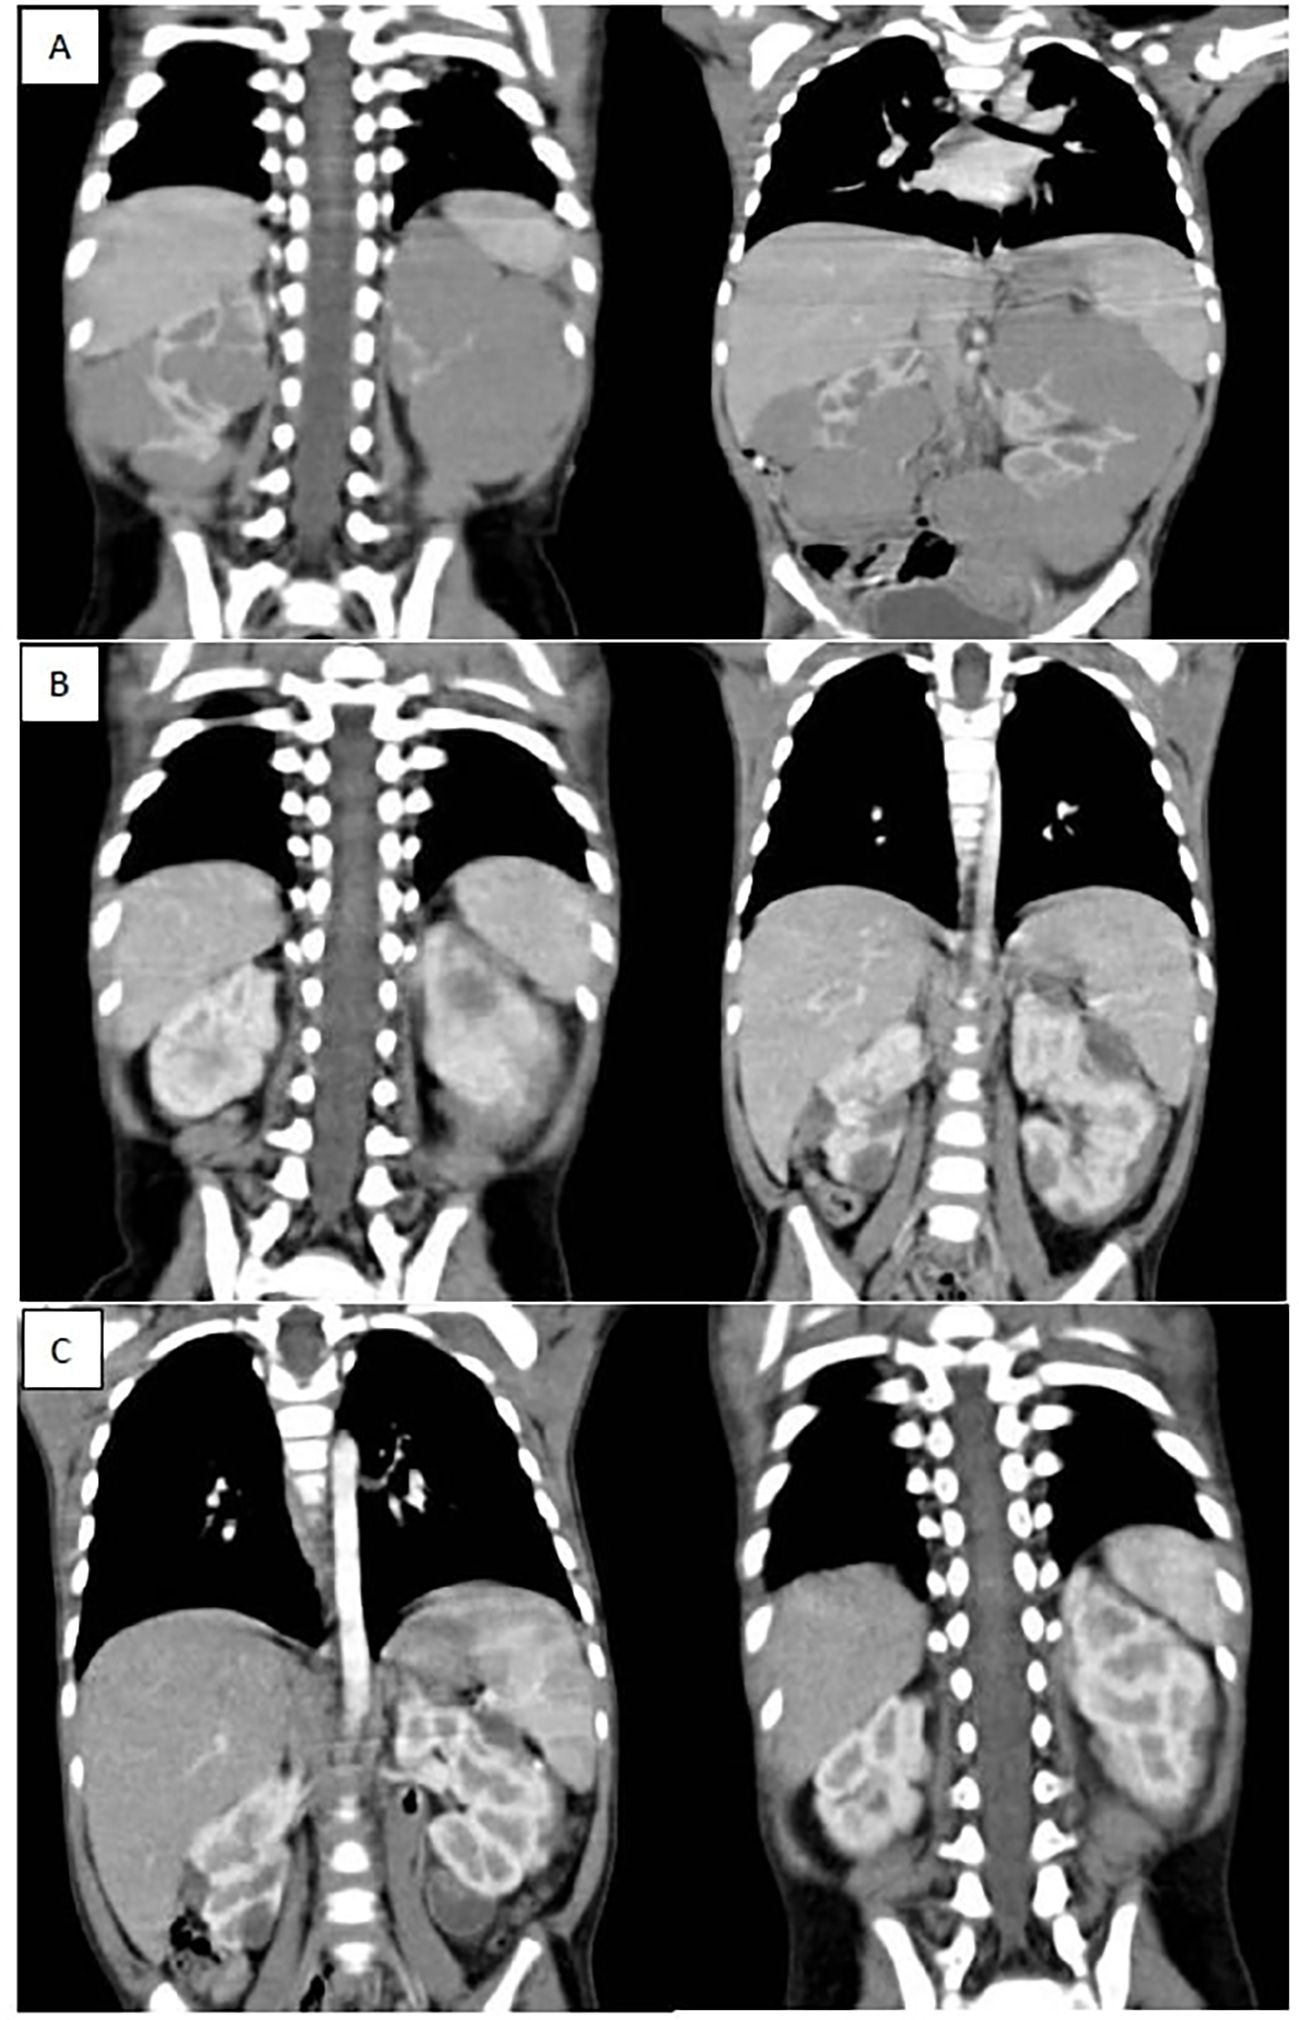

Out of 85 patients who achieved PR, 62 patients (72.9%) received 6 more weeks of chemotherapy and the response after 12 weeks chemotherapy showed that 59.5% of them (37/62) achieved further regression, while none of those who had SD (7/21) or PD (1/7) after 6 weeks showed any regression after addition of 6 more weeks. Of these 28 patients, 8 patients exhibited PR in the contralateral kidney. For those specific cases, our multidisciplinary team opted to administer an additional six weeks of neoadjuvant chemotherapy in the hope of achieving further response in the responding kidney to facilitate NSS for this kidney. However, this approach proved ineffective. (Figures 1, 2).

CT scans displaying coronal sections of the abdomen in three panels labelled A, B, and C. Panel A shows bilateral renal masses with the left kidney diffusely infiltrated with a huge mass while the right kidney shows multiple variable sized mass lesions, panel B shows marked regression of the bilateral renal masses after 6 weeks of neoadjuvant chemotherapy (average 90 % reduction of target lesions), panel C shows further regression of bilateral renal masses after 12 weeks of neoadjuvant chemotherapy.

Figure 2. (A) shows bilateral renal masses with the left kidney diffusely infiltrated with a huge mass while the right kidney shows multiple variable sized mass lesions, (B) shows marked regression of the bilateral renal masses after 6 weeks of neoadjuvant chemotherapy (average 90 % reduction of target lesions), (C) shows further regression of bilateral renal masses after 12 weeks of neoadjuvant chemotherapy.